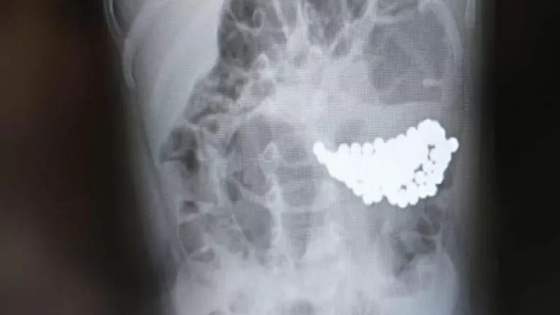

В Волгограде врачи спасли девочку, которая проглотила 134 магнитных шарика.

После обследования выяснилось, что причиной недомогания стала кишечная непроходимость, вызванная большим скоплением инородного тела. Магнитные шарики вызвали конгломерат, который сдавливал стенки кишечника.